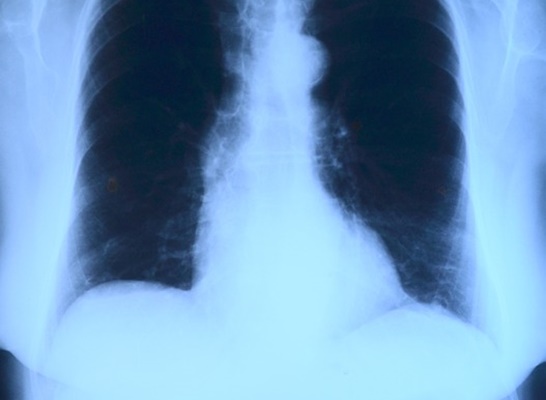

2. 기타부위 통증

흉부 통증 외에도 가슴과 어깨, 목, 팔 등에 통증이 나타난다면 이 역시 심근경색 초기증상일 수 있습니다.

팔이나 목 그리고 어깨 등이 장기간 아프면 보통 정형 외과를 가서 진단을 받곤하는데 정형 외과를 계속 다님에도 불편함이 지속 된다면 단순한 근육통 또는 관절 이상이 아니라 심근경색 초기증상으로 의심을 해보고 심혈관 질환 전문 병원의 진단을 받도록 해야합니다.

특히나 이러한 기타부위 통증 중에서도 목 주변 또는 심장과 가까운 팔이 주로 아픈 경우에는 더더욱이 빠르게 병원 진단이 필요한 상황임을 인지하시면 좋겠습니다.

또한 여성이나 당뇨병 환자의 경우 심근경색 초기증상으로 가슴에서 어깨와 목 그리고 팔 전반에 걸쳐서 통증이 확산되는 속도가 빨라 급성 심근 경색으로 증상이 나타날 수 있기도 합니다. 급성 심근 경색의 경우는 최대 3일간 통증이 지속되는 경우도 많습니다.